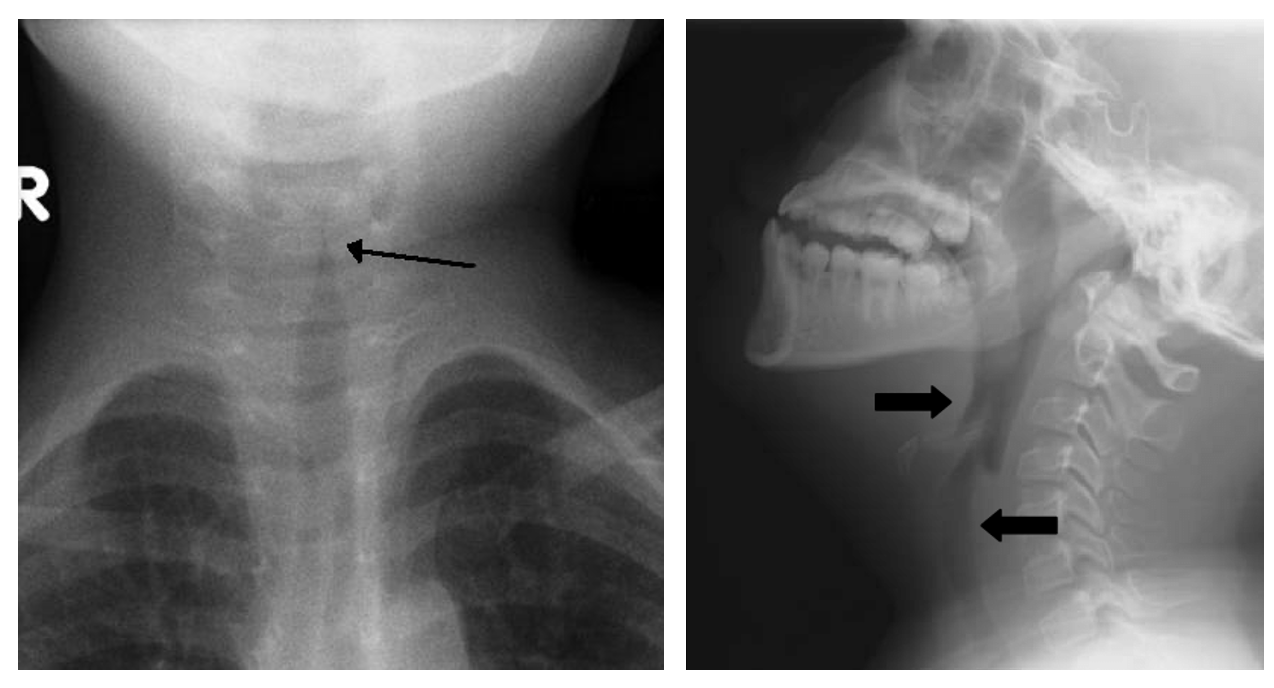

진단: 들숨 시 경부 측면 X선 → retropharyngeal space widening ± air fluid level

**정상 retropharyngeal space:

C2-C4 level에서는 vertebral body 두께의 1/3이하, 그 이하 level 에서는 vertebral body 두께와 같거나 얇아야 정상소견